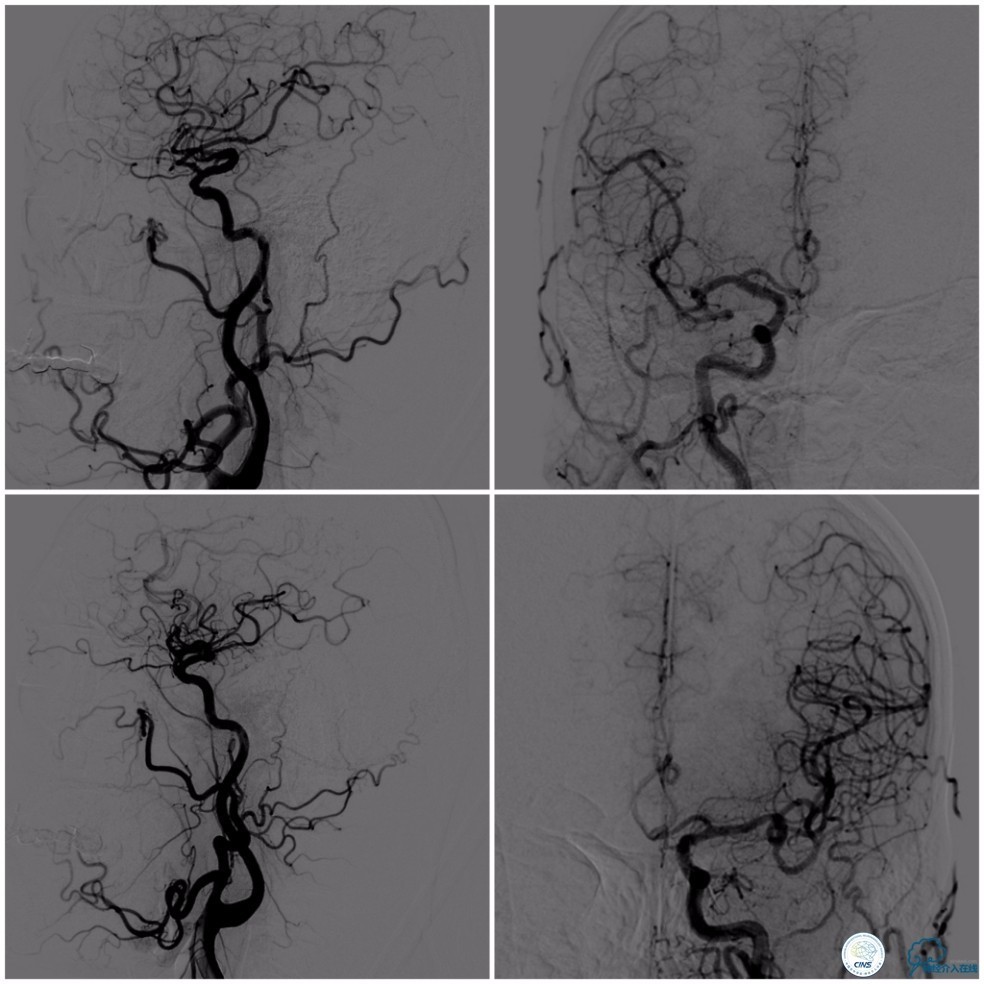

撤出Echelon-10微导管及5F导引导管。沿6F导引导管送入Select Plus微导管至基底动脉远端。经微导管送入Enterprise 4.5mm×28mm至右椎动脉V4段,两个支架重叠约2-3mm,完全覆盖右椎动脉V4段夹层(图13)。

图13

动脉粥样硬化狭窄合并动脉瘤的处理,因治疗狭窄和栓塞动脉瘤的两套系统常需要并列使用,事先要考虑所用导引导管是否能完全容纳两套系统,如本例8F导引导管到位困难,故只能改用两套系统完成治疗(图14)。

图14